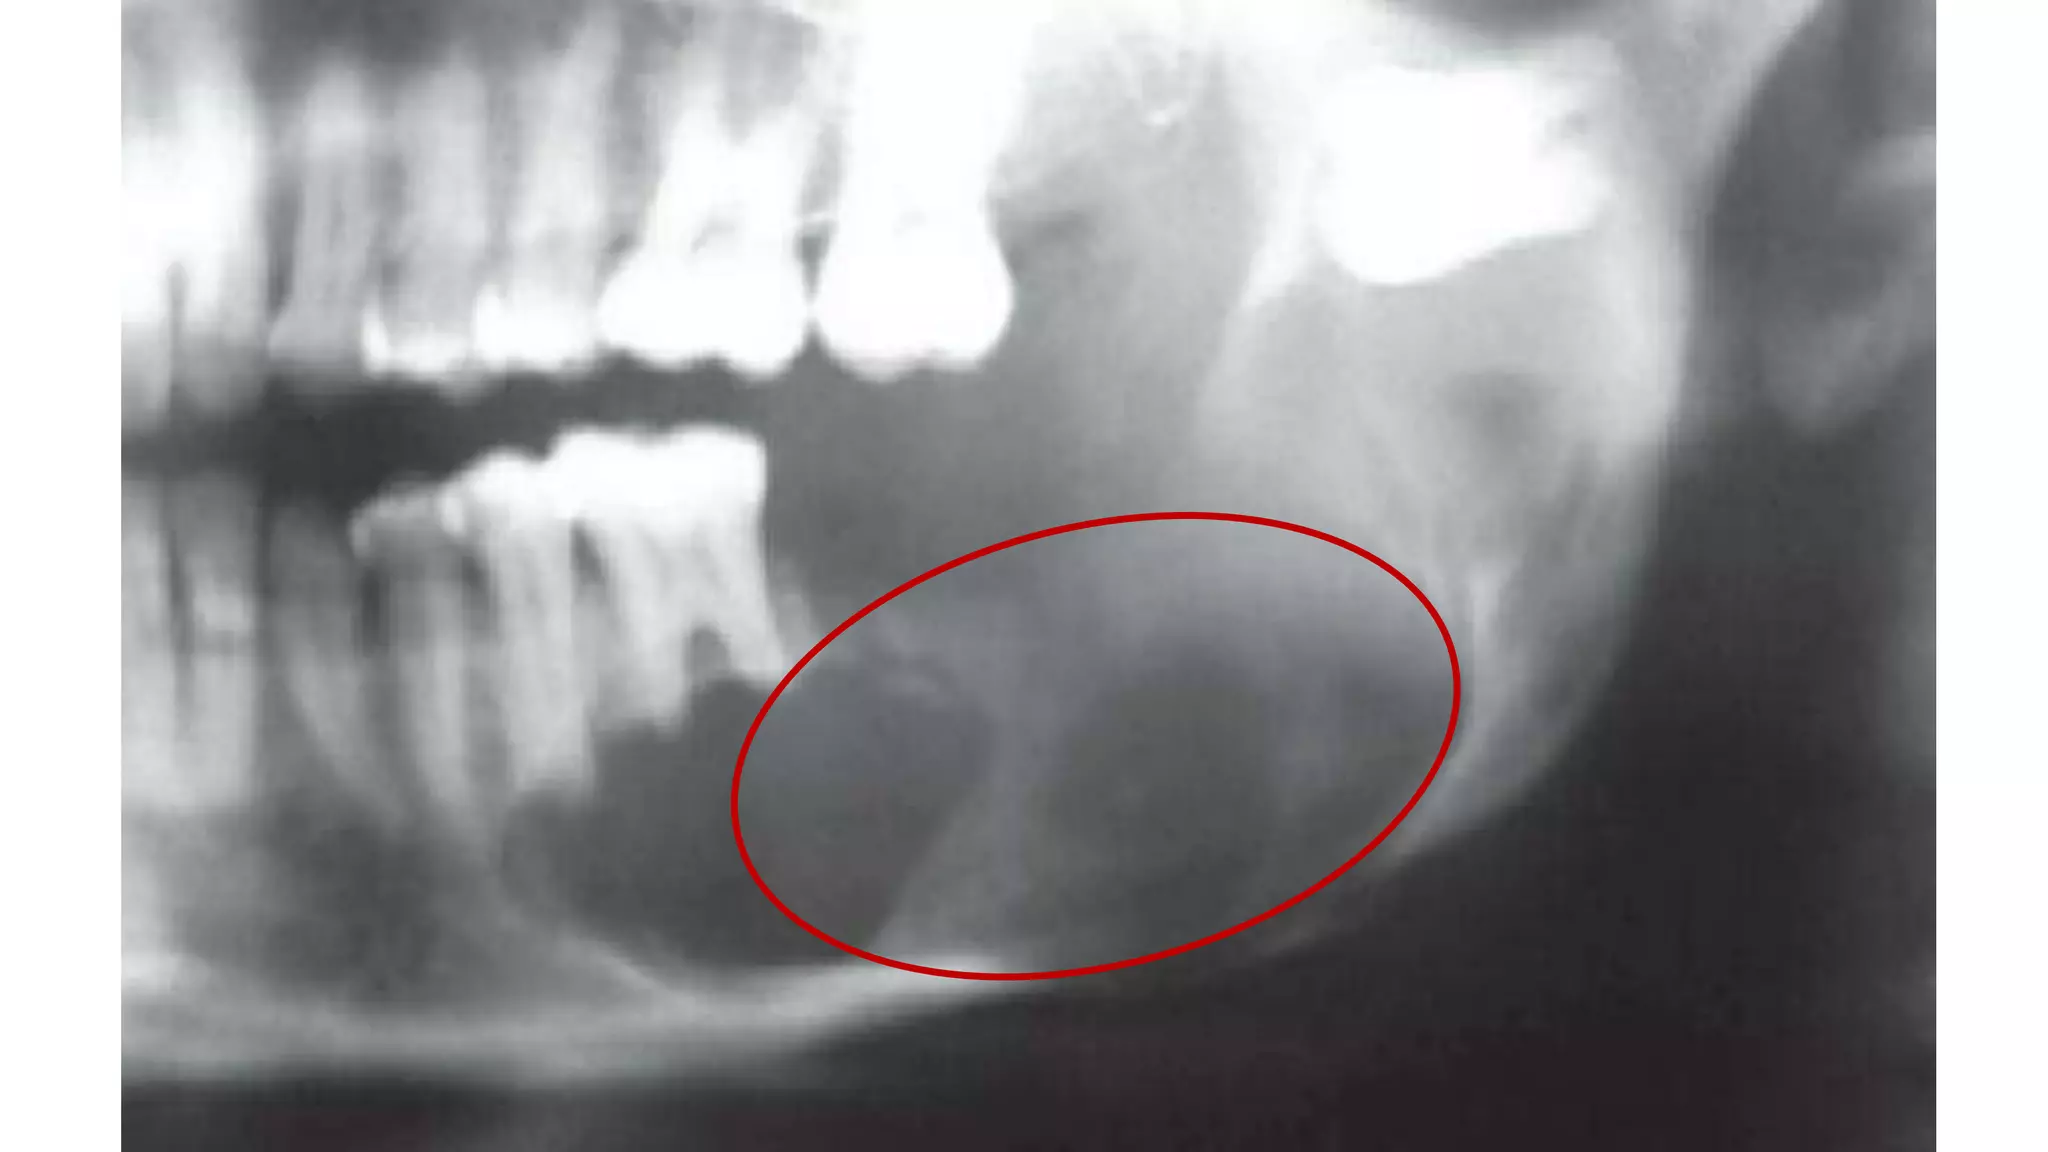

АМЕЛОБЛАСТОМА

Амелобластома – это доброкачественная одонтогенная опухоль челюстно-лицевой

локализации, вызывающая деструкцию костной ткани. По мере развития

амелобластомы возникает асимметрия лица, происходит постепенная деформация

челюсти, расшатывание и смещение зубного ряда

АМЕЛОБЛАСТОМА Амелобластома – этодоброкачественная одонтогенная опухоль челюстно-лицевой локализации, вызывающая деструкцию костной ткани. По мере развития амелобластомы возникает асимметрия лица, происходит постепенная деформация челюсти, расшатывание и смещение зубного ряда